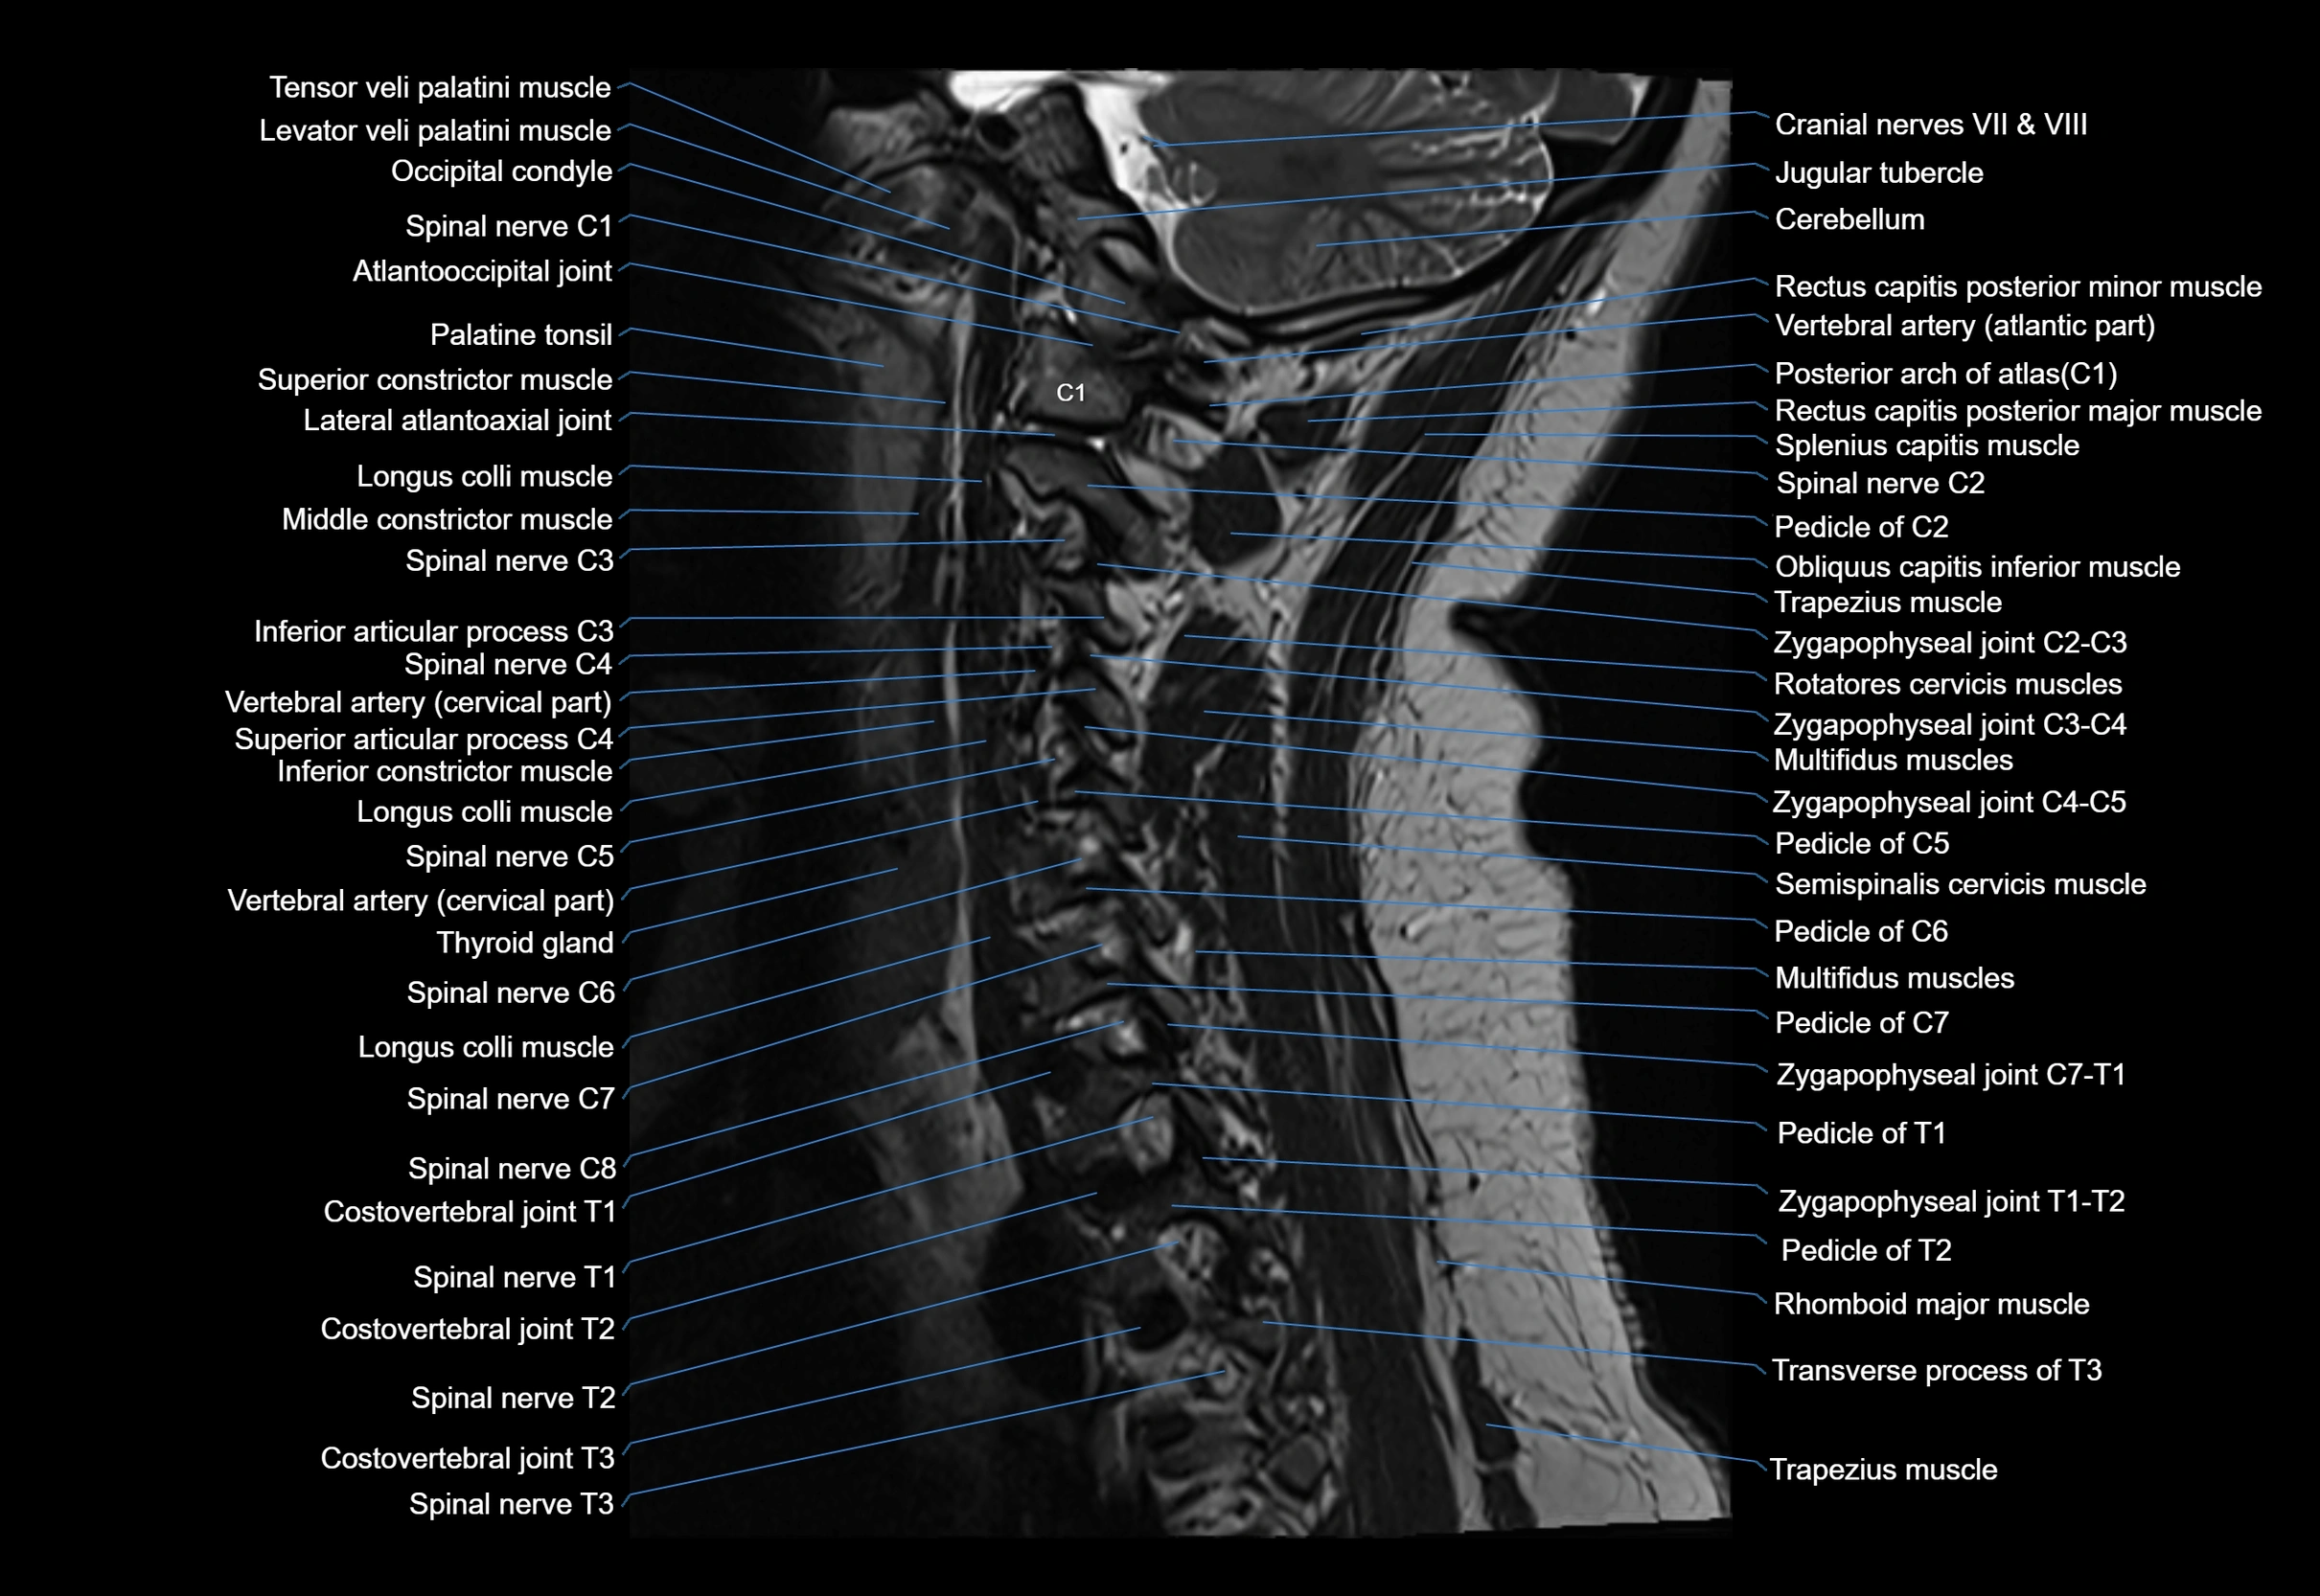

MRI image

image